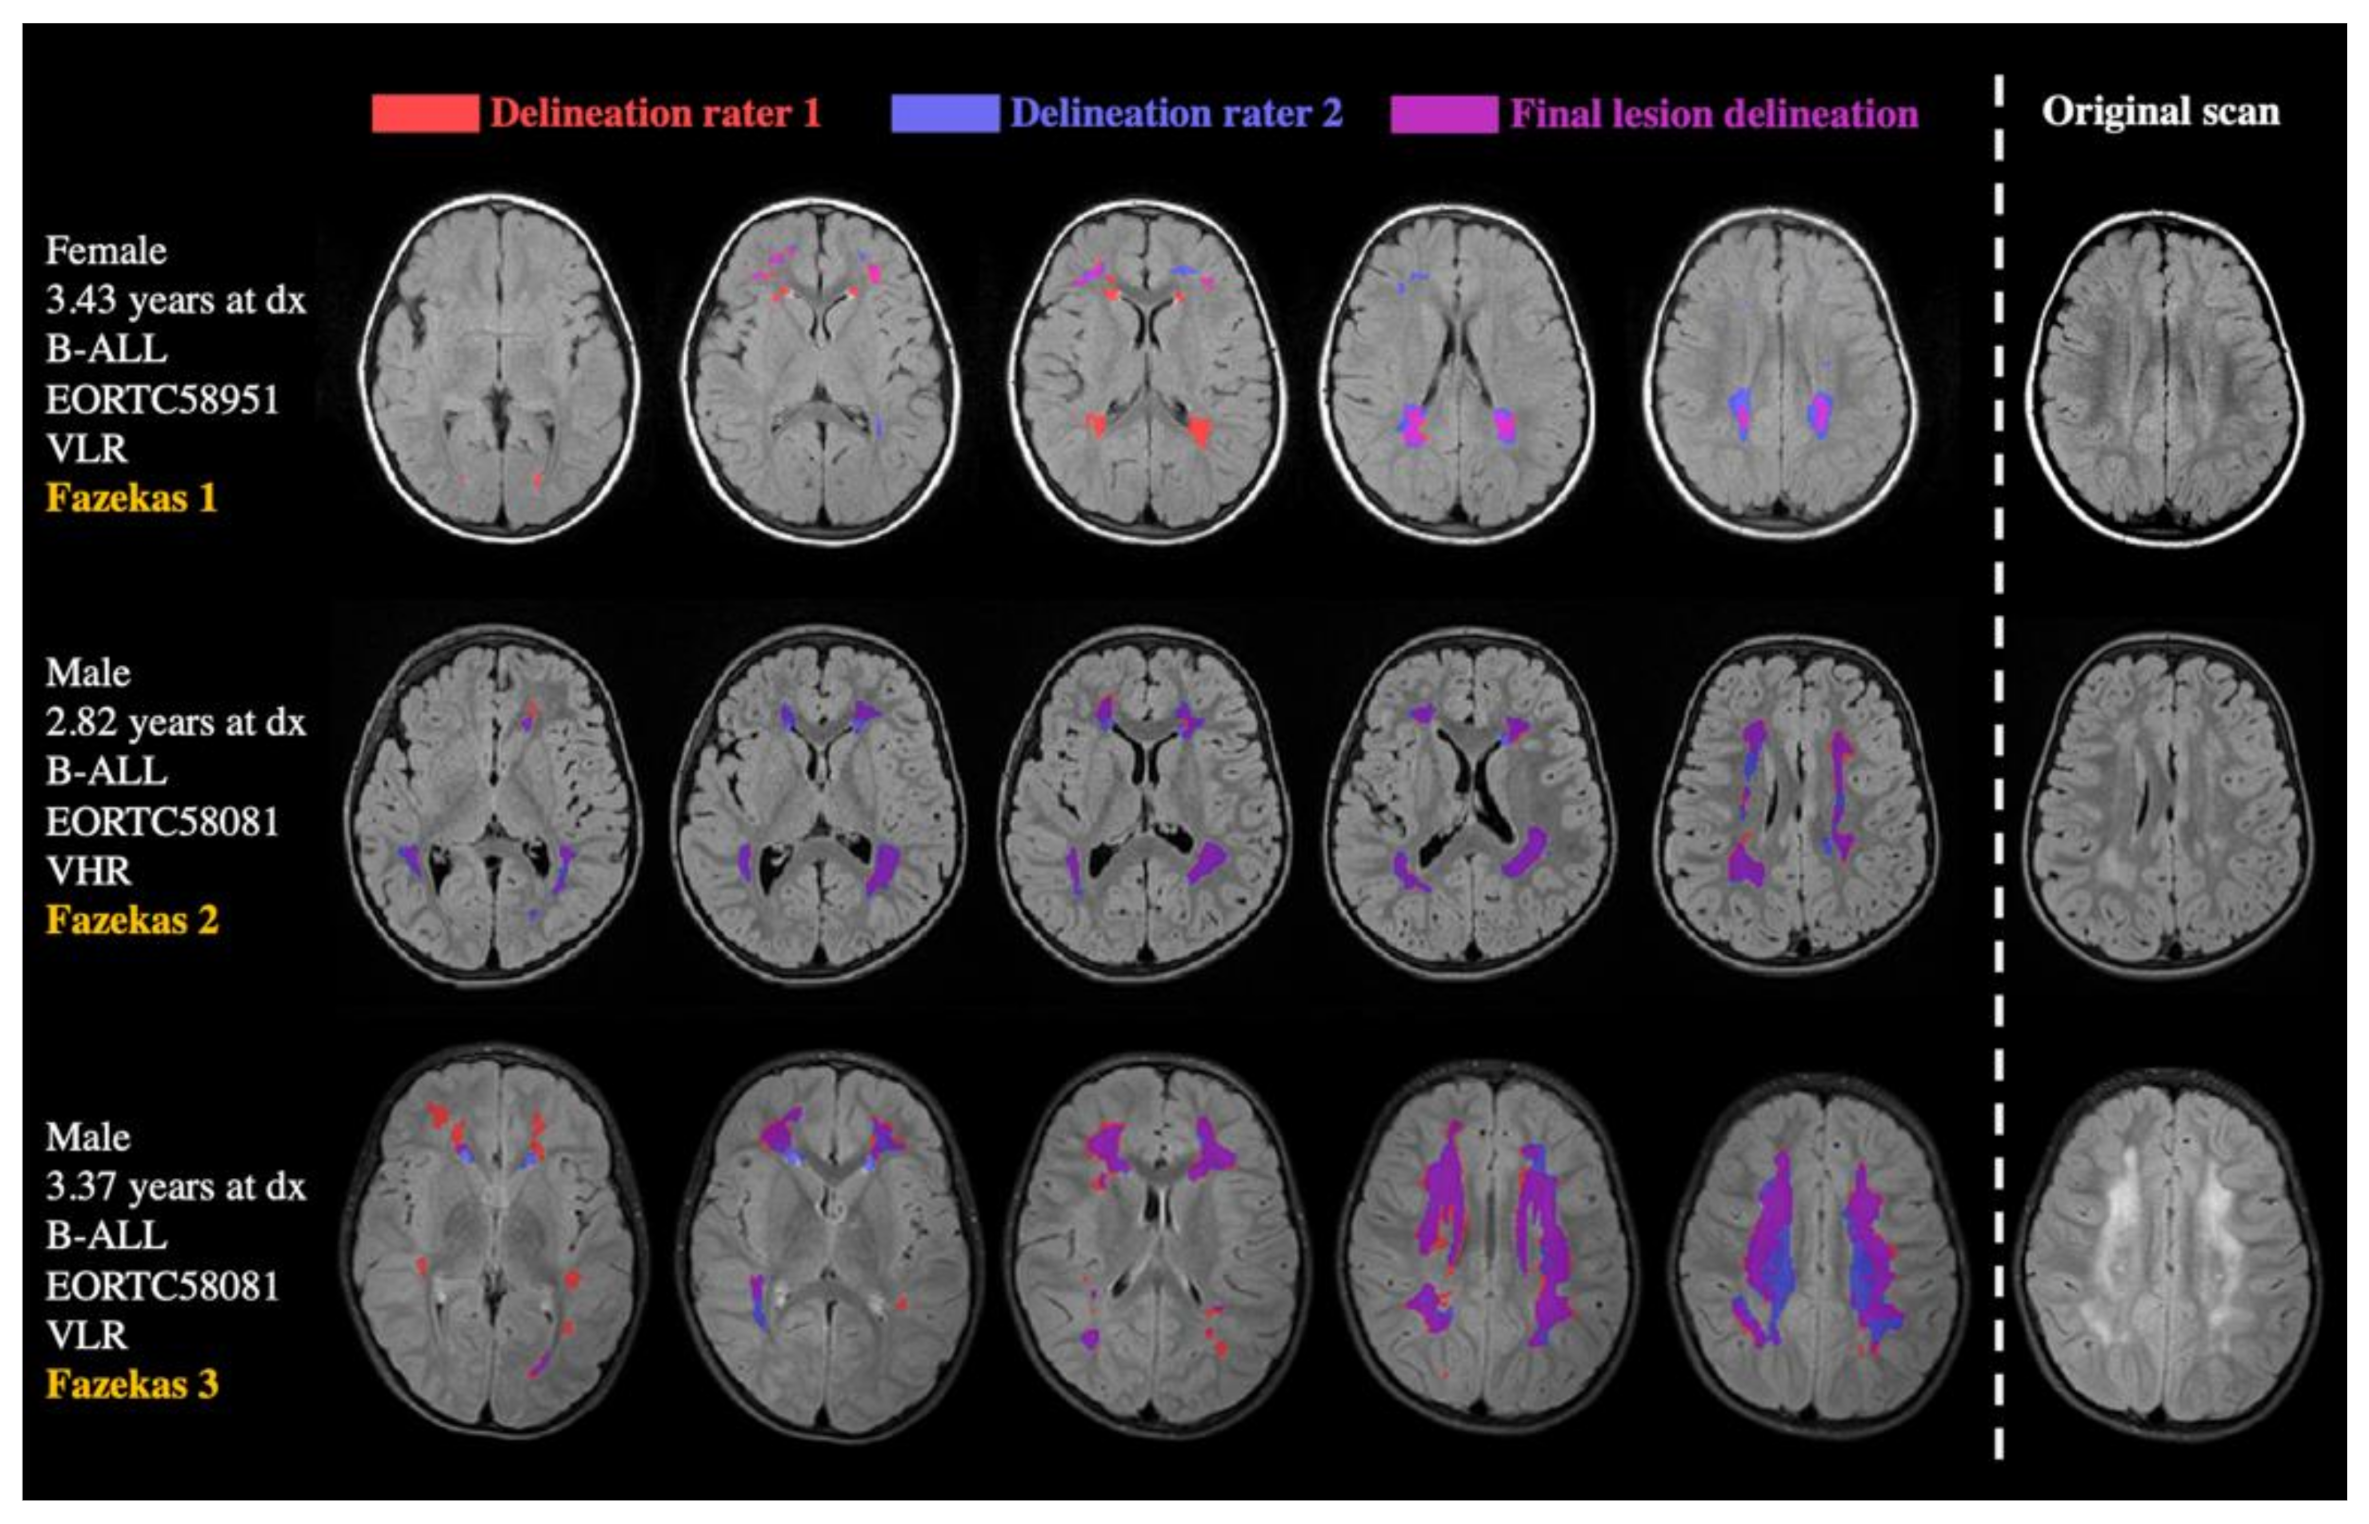

2.3. Data Analyses